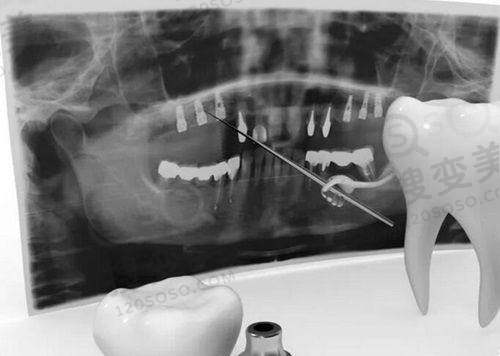

苏州博雅口腔诊所是经相关部门审批成立的正规私立口腔诊所。它日常诊疗时间灵活,能满足广大患者的需求。诊所拥有现代化设施和前列的口腔医疗技术,积极引进国内外精良设备,如 CBCT 机、全景机等,为医生的诊疗奠定了良好基础。医资力量上邀请了国有医院的医生前来坐诊,常见牙齿诊疗项目都能开展。其环境装修干净温馨,工作人员热情,针对患者问题会详细解答,在当地口碑非常好,是具有竞争力的口腔门诊之一。

苏州博雅口腔诊所的特色项目及技术优势显著。其一,种植牙技术堪称行业翘楚,采用 3D 数字化种植导航技术,能有效保护种植体植入位置的精细度,极大提升种植手术成功机率。其二,牙齿矫正技术精良,运用精密的矫治设备和科学的力学原理,可有效矫正各种错牙畸形,为患者塑造良好的牙齿排列和面部曲线。此外,诊所还拥有精良的医疗设备,如 CBCT 机、全景机等,为正确诊断和治疗提供了保护。